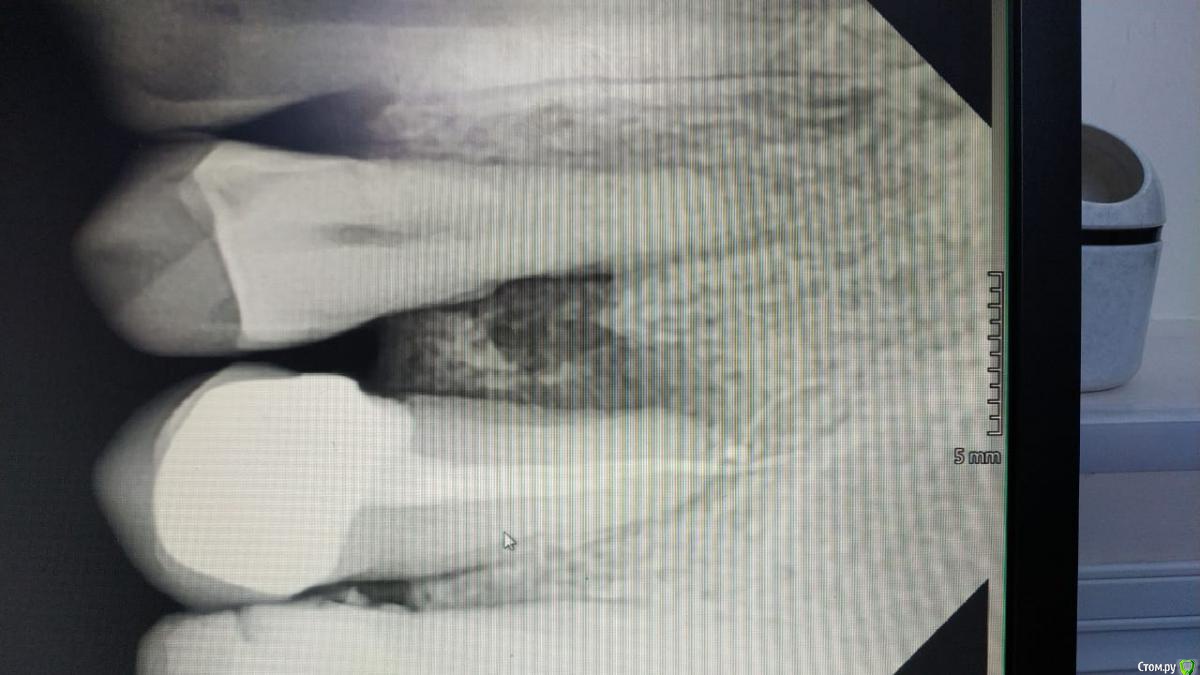

kuziy12 Опубликовано 22 февраля, 2020 Поделиться Опубликовано 22 февраля, 2020 Здравствуйте. Подскажите как лучше поступить. За качество фото извиняюсь, сел акум на основном. Телефон наше все.. Анамнез: 6 месяцев назад поставили мышьяк не очень герметично, неделю пациент ходил, так как не мог записаться. После попал ко мне. Эндо лечение зуба 2.5, удаление распада сосочка, добился крови из кости. Так как пациентка уезжала, постоянная коронка. Объективно:Межзубной сосочек отсутствует, секвестр подвижен, зуб 2.4 и 2.5 - подвижность I степени, перкуссия безболезненна. Сопр без особенностей. Вестибулярная кортикалка между зубами отсутствует. Зуб 2.4 живой. От себя: Если от мышьяка, то почему без острой стадии и как он так интересно подействовал в глубь кости, а не на поверхности? Точно не помню, но вроде в каналах пульпа была живая. Примерная тактика: откинуть лоскут, удалить секвестр, кюретаж. Имеет смысл подсыпать искусственную кость? Ссылка на комментарий

kuziy12 Опубликовано 8 марта, 2020 Автор Поделиться Опубликовано 8 марта, 2020 Как то так. Попытался вообще без откидывания, но тогда бы секвестр десну порвал, большой слишком. Уже его чуть сдвинул:Убрал грануляции:Ушился:Это секвестр: 3 Ссылка на комментарий